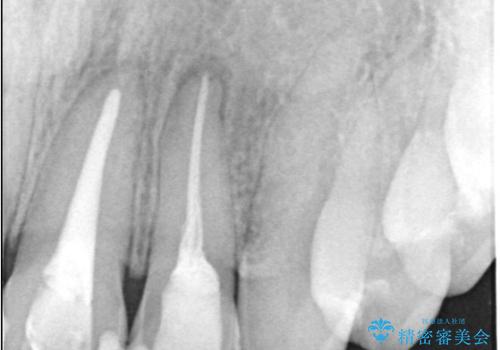

左上1番および2番は失活歯であり、両歯ともに失活に伴う変色を認めました。左上2番に関しては根尖部に透過像を認め、根尖性歯周炎と診断しました。これが前歯部の痛みの原因と考えられました。

左上2番に対して精密根管治療を実施し、感染源の除去を行いました。その後、左上1、2番ともにオールセラミッククラウンによる補綴を行い、審美的な修復を行いました。

根管治療では、ラバーダム、マイクロスコープ、根管をしっかり洗浄するための専用器具の使用が必須となる治療です。

徹底した洗浄により高い治療効果が得られます。